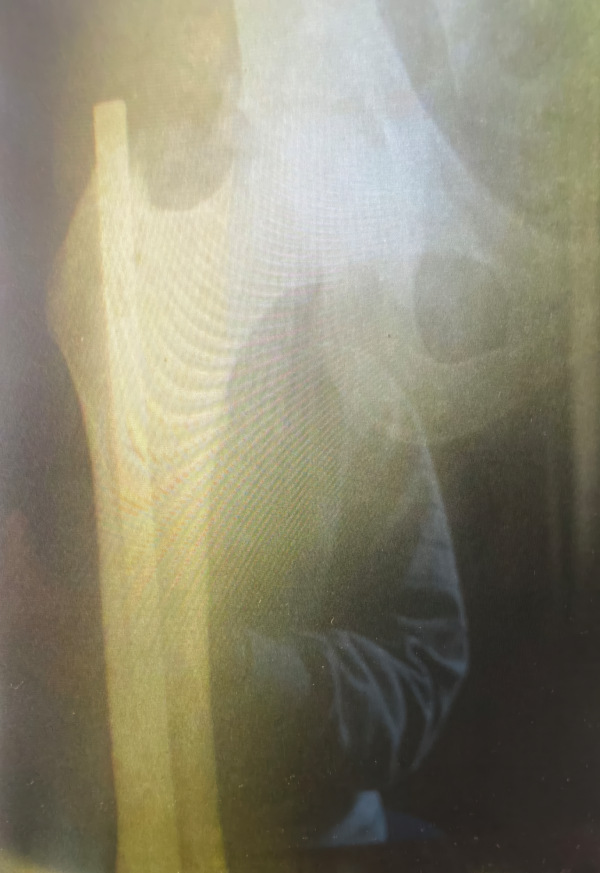

Abstract Image